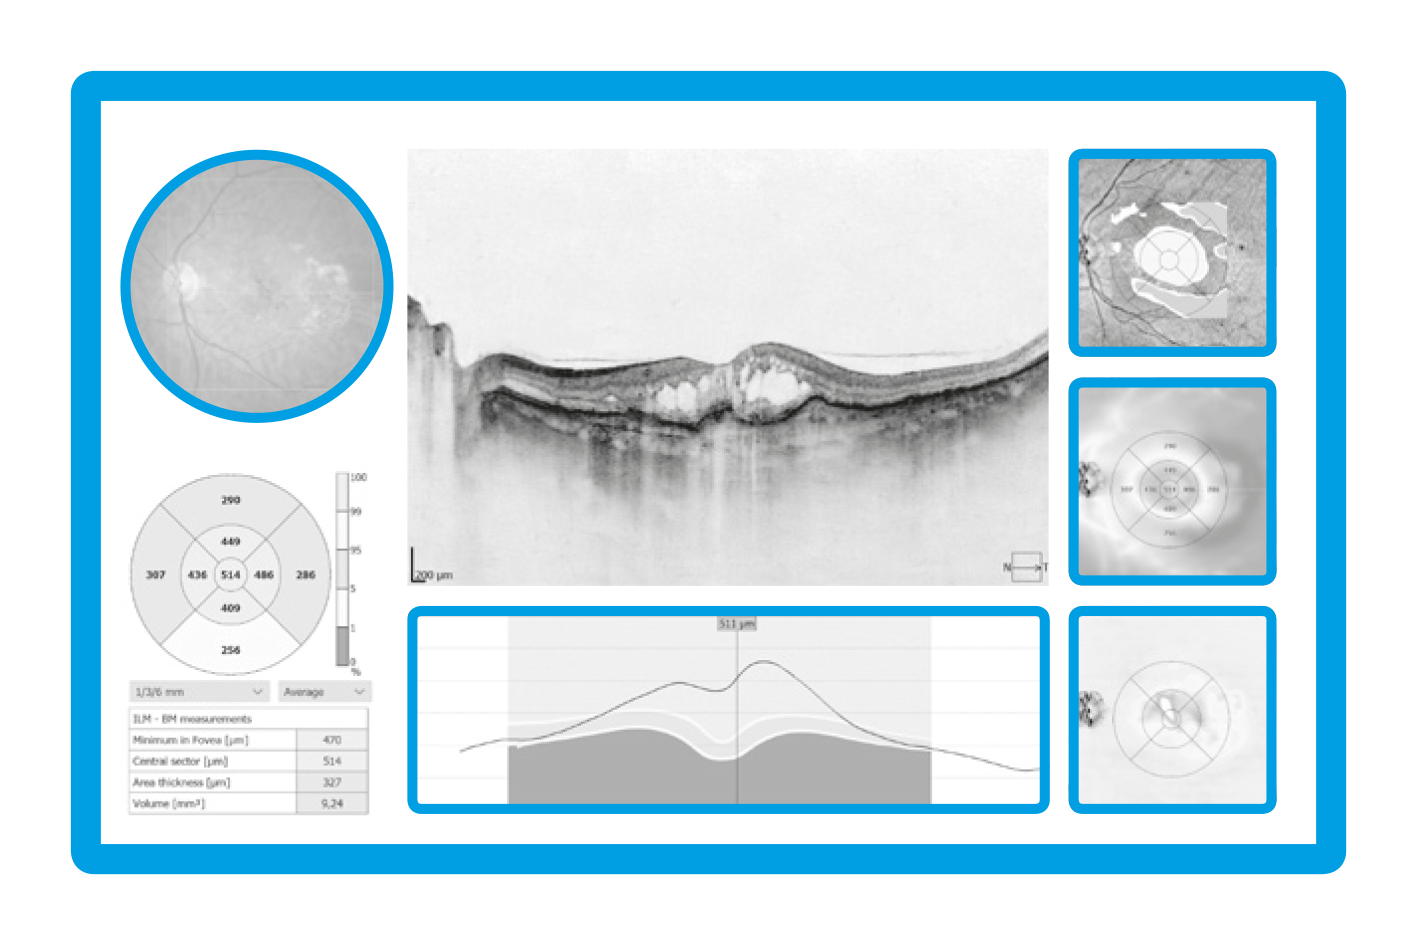

AI Retina

AI-based segmentation of the posterior segment enables automatic detection and analysis of up to 12 retinal layers, resulting in more accurate recognition of retinal layer boundaries. The AI system supports precise structural assessment and improves evaluation of pathological changes within the retina.

A single Widefield 3D examination is now sufficient for the rapid assessment of both the retina and the optic nerve head, reducing examination time and eliminating the need for multiple separate scans.

Visualize and assess the thickness of the retina, ganglion cell layer, nerve fiber layer, and optic nerve head on a comprehensive data report when performing widefield mapping up to 15 × 15 mm.

The widefield report presents horizontal and vertical tomograms and includes optic disc topography, supporting efficient evaluation and follow-up of glaucoma patients.